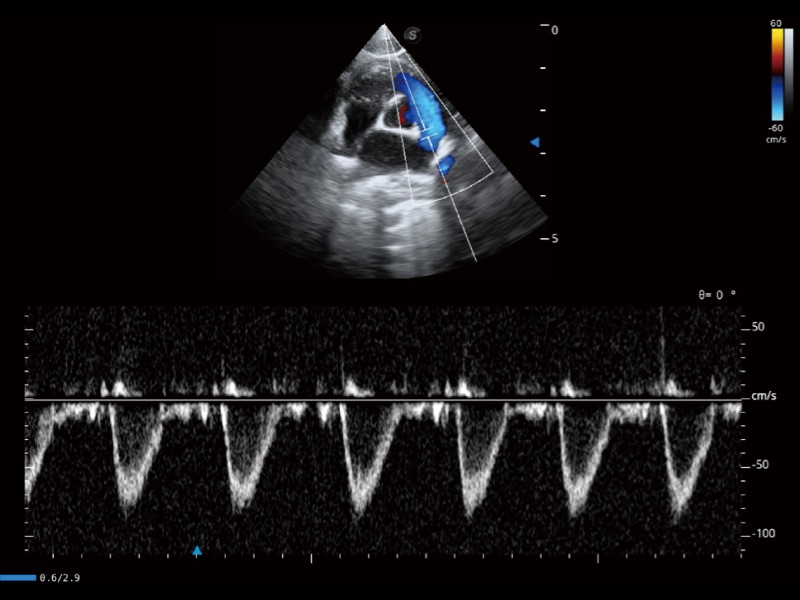

通過創(chuàng)新的 Matrix E自適應(yīng)濾波器和超長時(shí)間域算法,極大提升超低速微細(xì)血流的檢出能力,同時(shí)更精準(zhǔn)地濾除軟組織和噪聲信號,為獸用醫(yī)生提供以往無法通過常規(guī)血流獲得的疾病診斷信息。